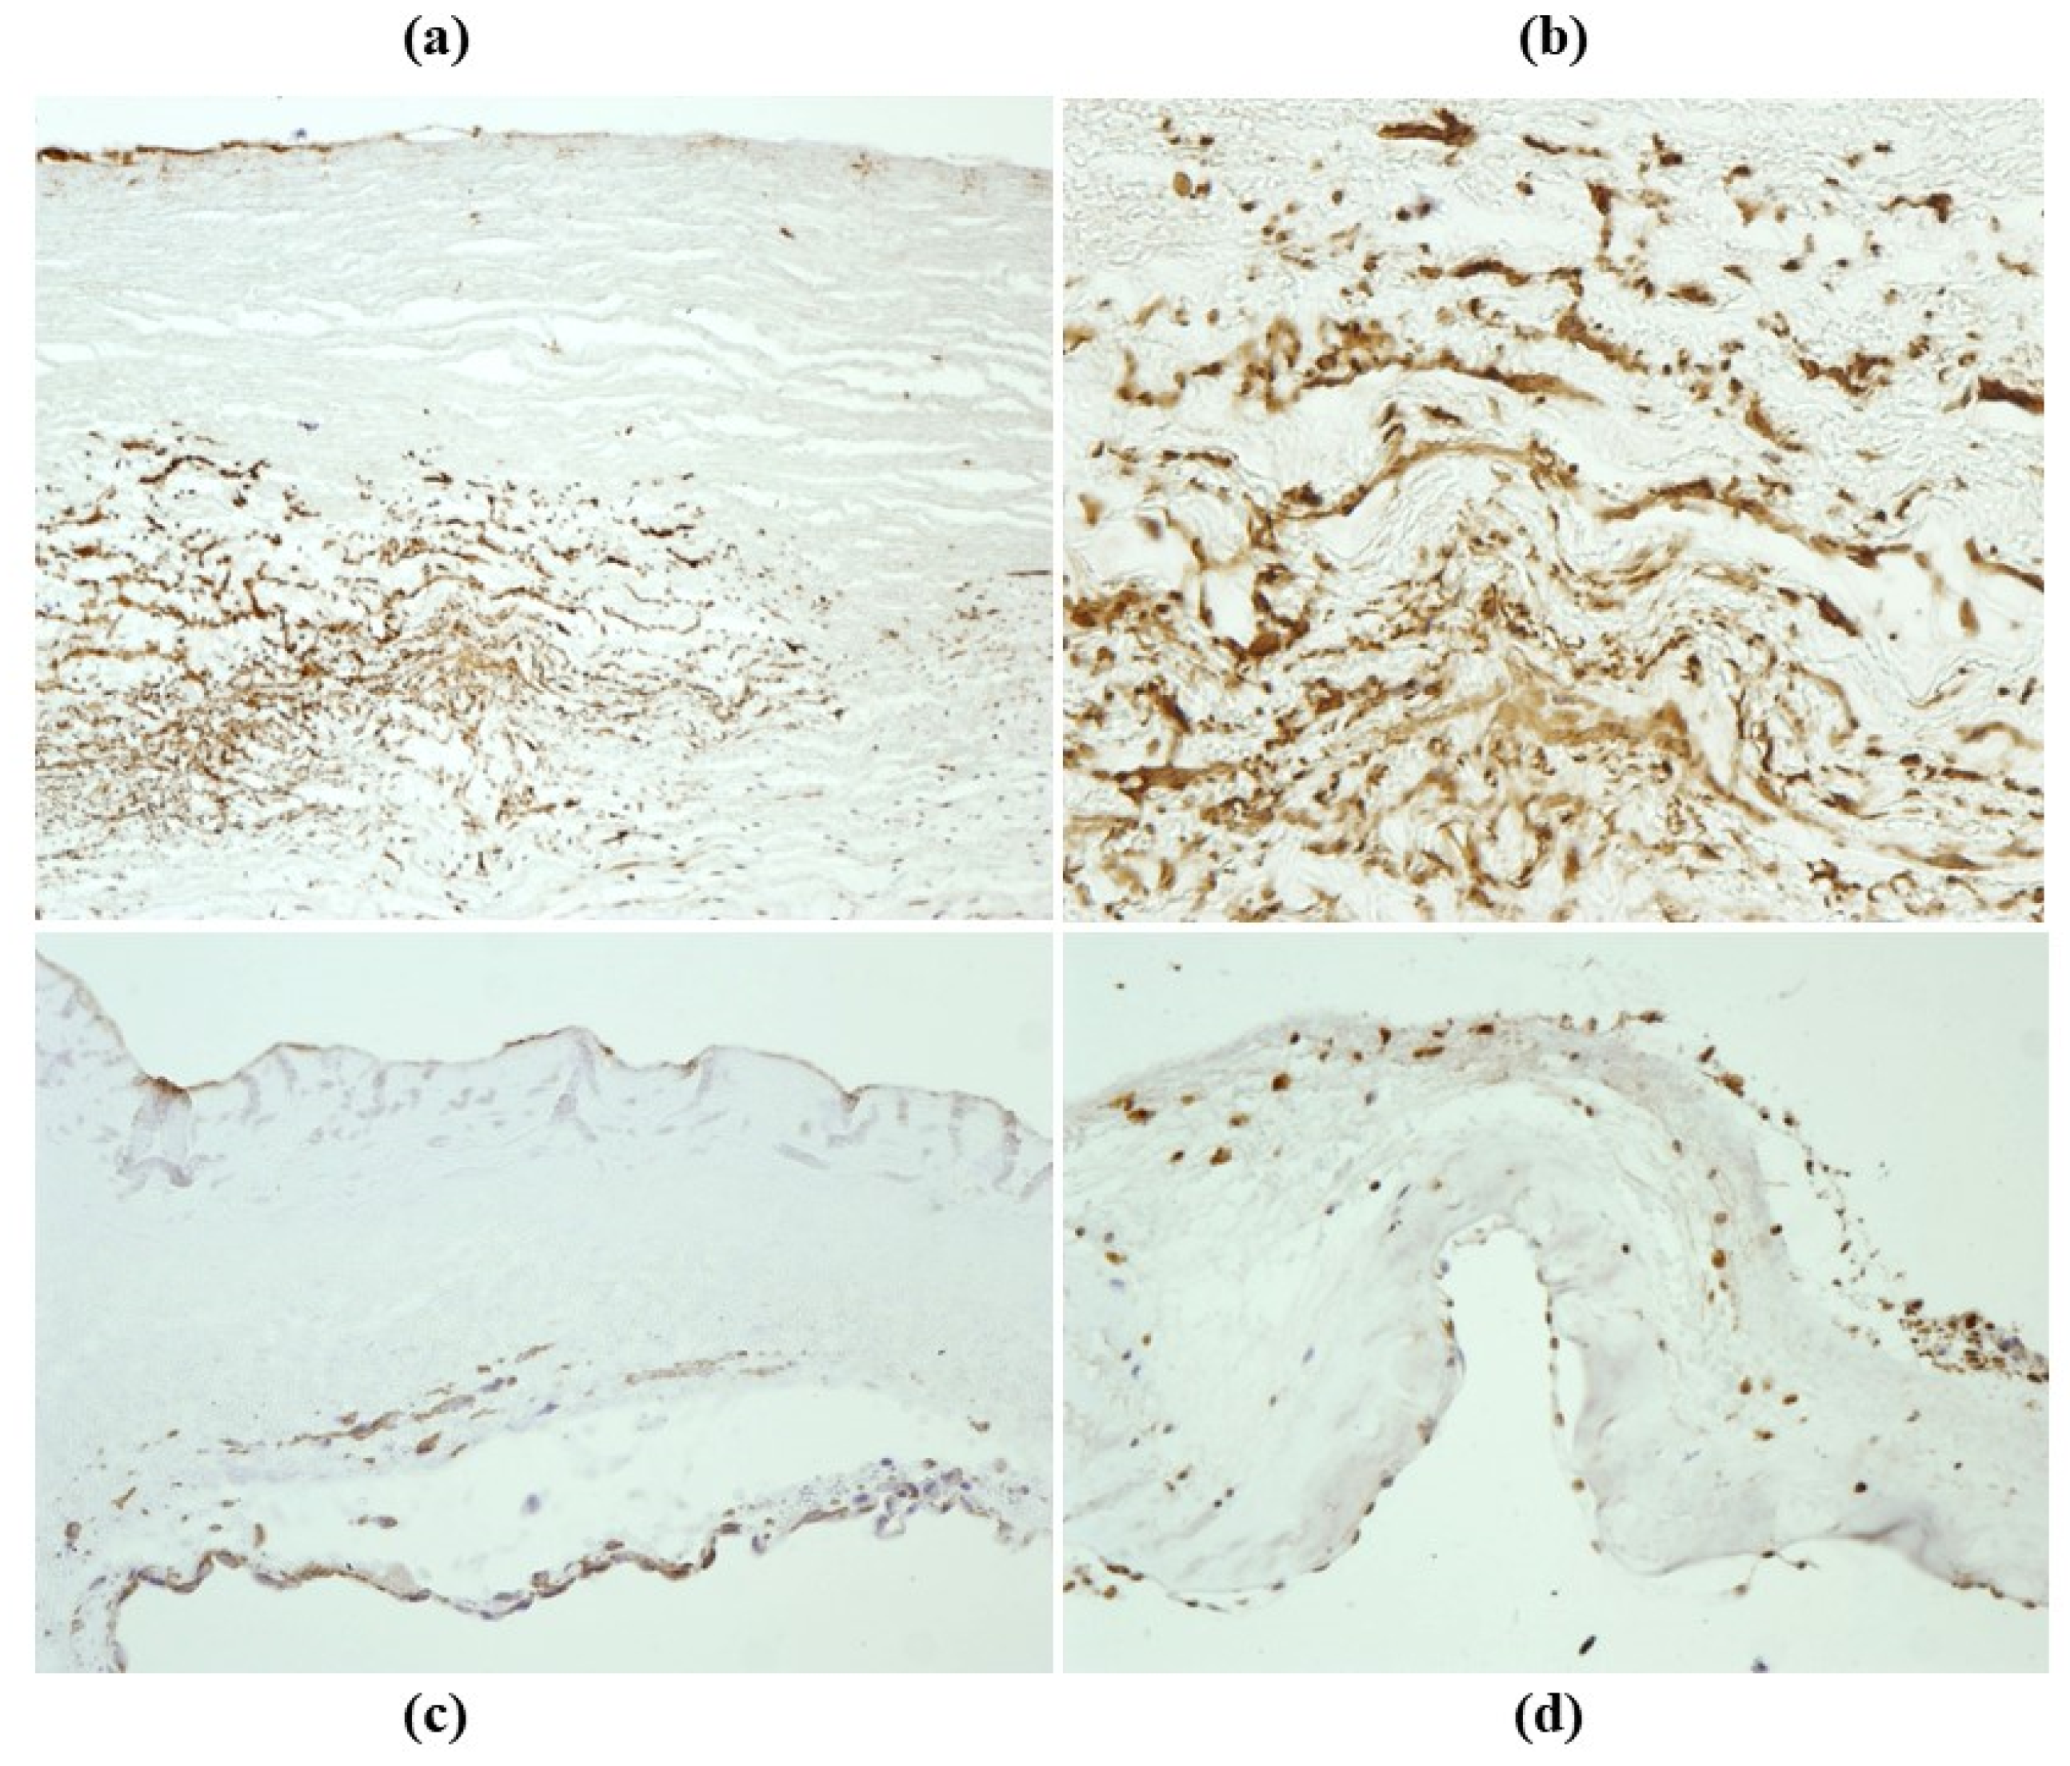

- Cellular repopulation was observed in the outer part of implanted homograft wall by novel smooth muscle cells in the lamellar units (Figure 32a,b) and in the intima with a novel myointimal layer; this layer was noticed also in small animals such as rodents [68]. Novel endothelial cells appeared to line both the aortic wall intima and inflow/outflow at the cusp surface, as well as vasa vasorum, and valve spongiosa appeared repopulated by interstitial cells (Figure 32c,d);

- The undifferentiated nature of the repopulated cells is demonstrated by colocalization of some biomarkers. Novel wall cells showed positivity both for α-SMA and vimentin and novel cusp cells for SMA, vWF, VEGF, VEGF R2, α-SMA and CD57 (HNK-1), which is a neural crest marker;